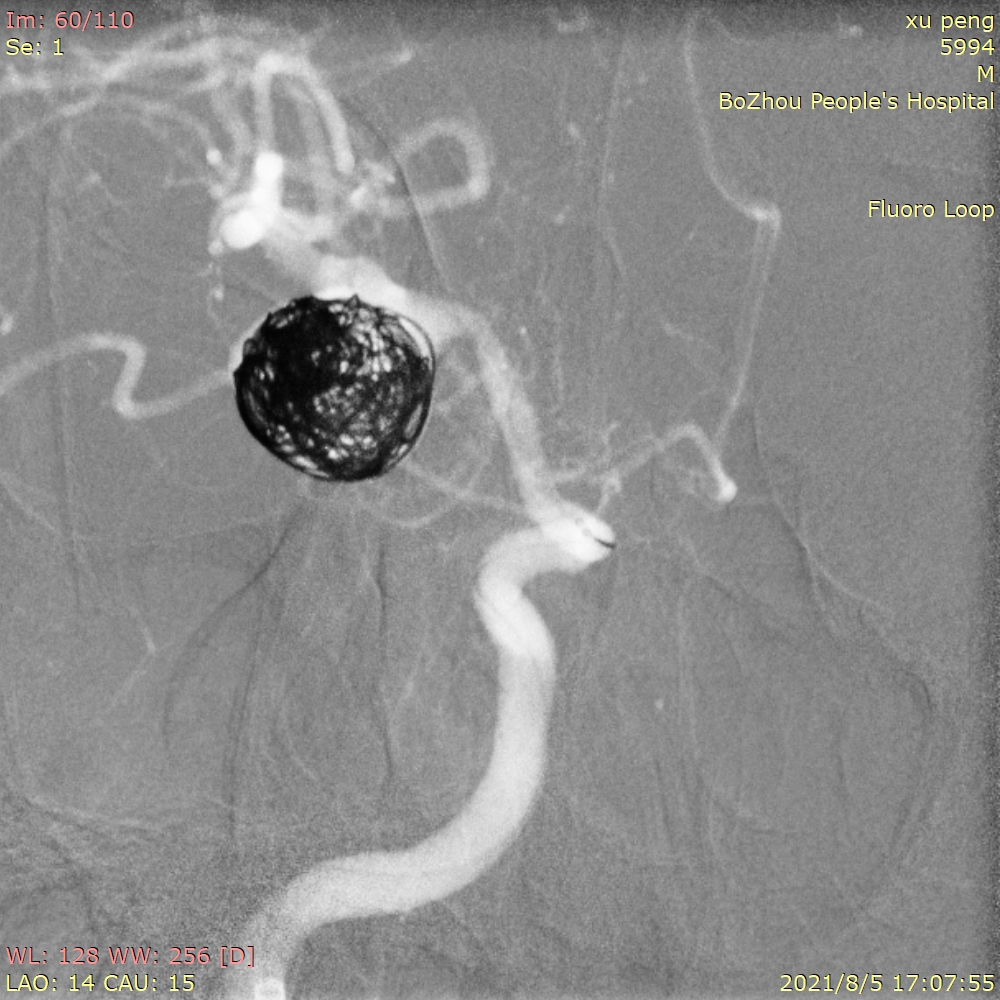

工作位造影

先将第一根SL-10微导管塑形成“猪尾”后,顺利送入动脉瘤体内中心位置。我们打算先用一根微导管进行填圈,如果填圈顺利就不使用双导管技术。

选用Target 15/30作为成篮圈,经过小心、缓慢推送弹簧圈,使第一个圈的成篮形态和位置非常完美,弹簧圈瘤内完美贴壁,也基本覆盖瘤颈。

成篮圈的即刻造影和蒙片